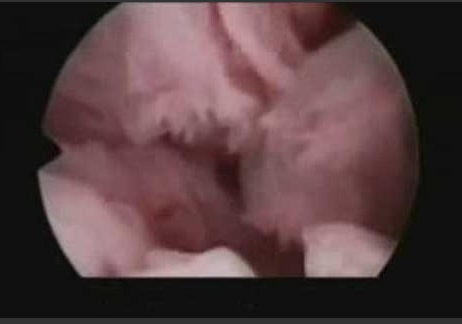

内窥镜揭秘 卵子排出的真实图片

卵子排出的真实图片

我们即将目睹排卵的全过程

现在正在输卵管中朝着卵巢前进